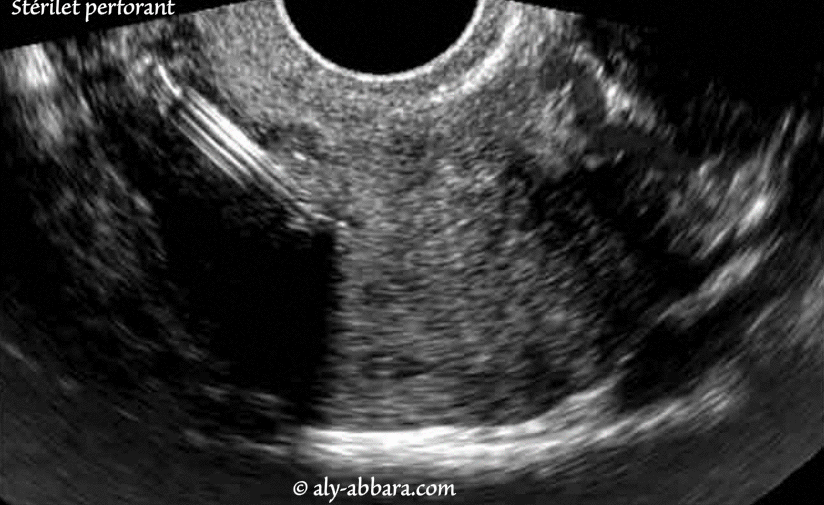

| Stérilet perforant (faux trajet) |

Dispositif intra-utérin de type hormonal (DIU) perforant la paroi latéral droite de l'utérus au niveau de la région supra-isthmique et atteignant le paramètre utérin droit.

Il s'agit d'une perforation utérine par le dispositif intra-utérin survenant lors de son insertion. Il s'agissait d'une pose difficile en raison de la latérodéviation du corps de l'utérus vers la gauche. Cette complication fut découverte, 48 heures après la pose du stérilet, lors d'un contrôle échographique systématique devant les difficultés rencontrées lors son insertion et les doutes sur éventuel faux trajet, mais il est bien à savoir que cliniquement, la patiente ne se plaignait d'aucune douleur ou métrorragie inhabituelles. Le retrait du dispositif intra-utérin a été réalisé sans incident. |